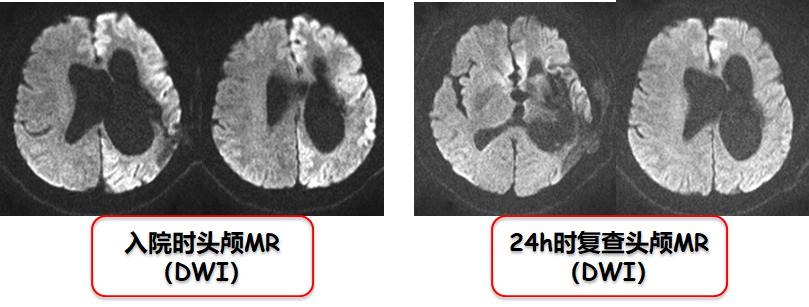

男性,67岁,“突发四肢抽搐伴意识不清1小时”急诊入院;脑卒中后遗留右侧轻偏瘫;有癫痫发作史,未规律服用抗癫药;抗癫痫治疗很快缓解,影像学复查完全恢复。

图3:患者DWI(源自曹勇军教授讲课PPT)

那么,这是一个很明显的痫性发作的类卒中患者。至于Todd瘫痪性类卒中的鉴别诊断要点,曹勇军教授归纳如下(表1)。